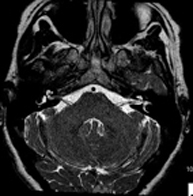

- RM Cerebral (craneal)

Prueba diagnóstica no invasiva que consiste en la obtención de imágenes de alta definición anatómica del cerebro mediante el empleo de un campo electromagnético y ondas de radio (con un emisor y un receptor). No utiliza radiación ionizante. Indicaciones: problemas vasculares, pérdida de memoria, epilepsia, cefalea, malformaciones, sospecha de tumor, meningitis.